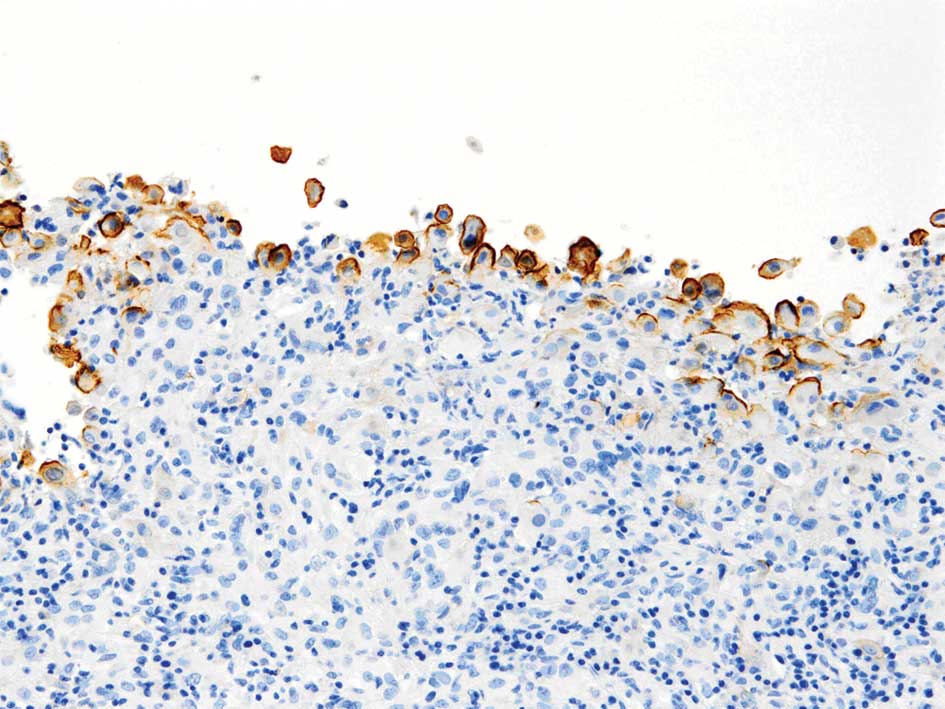

What mesothelioma is cancer research uk. Mesothelioma is a type of cancer that can develop in the tissues covering the lungs or the abdomen. It is a cancer of mesothelial cells. These cells cover the outer.

Mesothelioma is a type of cancer that develops from the thin layer of tissue that covers many of the internal organs (known as the mesothelium). The most common area. Clinical screening guidelines for asbestosrelated. Financial assistance available. Pleural mesothelioma pleuralmesothelioma. Malignant pleural mesothelioma search now! Over 85 million visitors. Pleural mesothelioma cancercenter. Connect with us and get the best information on mesothelioma cancer. Asbestos settlements. Pericardial mesothelioma makes up fewer than six percent of all recorded mesothelioma cases. Like pleural and peritoneal the importance of mesothelioma screening. Mesothelioma wikipedia, the free encyclopedia. Mesothelioma is a type of cancer that develops from the thin layer of tissue that covers many of the internal organs (known as the mesothelium). The most common area.